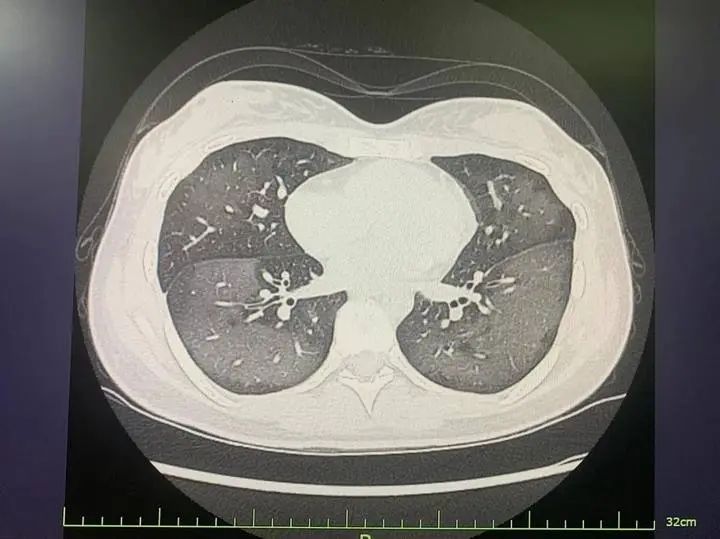

20岁姑娘查出“白肺”

浙江绍兴一位20岁的姑娘,

因使用防晒喷雾不当,

竟查出“白肺”,

得了急性过敏性肺炎。